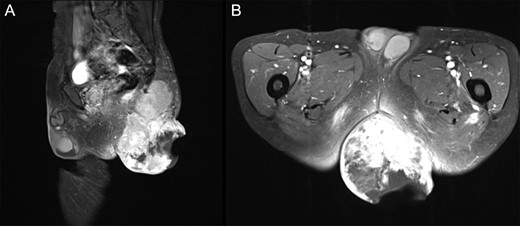

T1WI contrast-enhanced MRI with fat suppression at first visit. (A) Sagittal image. (B) Axial image. Left gluteal region: a 15 cm tumor extending from the gluteus maximus muscle to the subcutaneous tissue with enhancement of irregular margins was observed. A portion of the tumor had disintegrated, and the internal mass was heterogeneous.